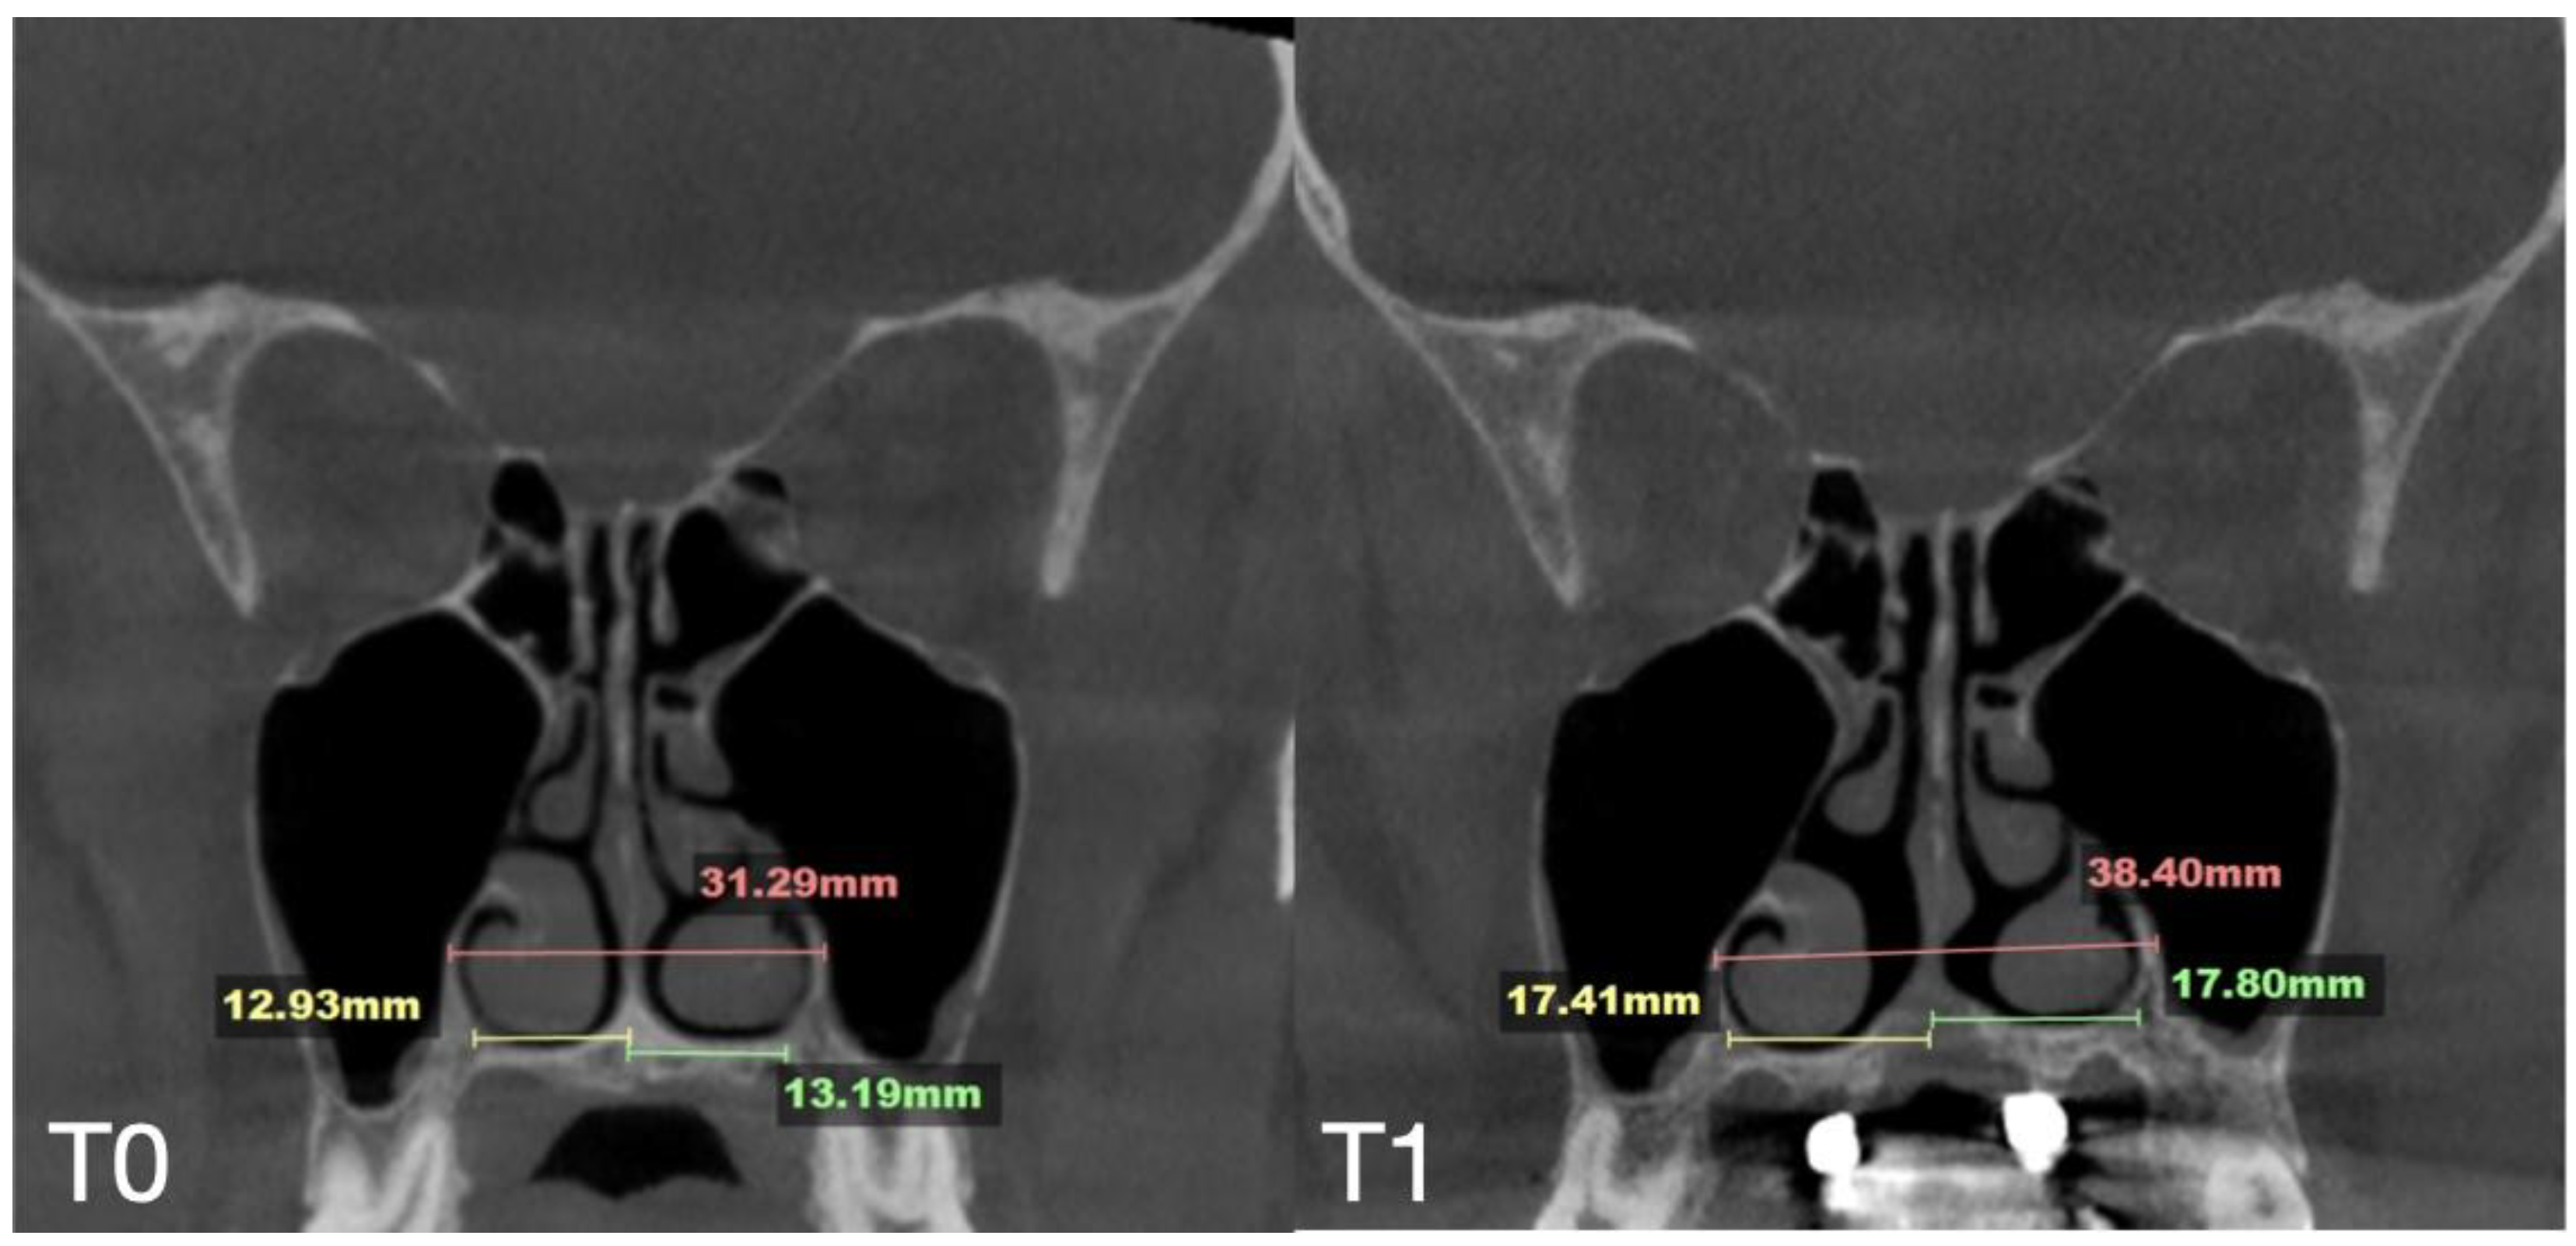

| Case C | 28.40 | 38.32 | 36.72 | 53.63 | 62.43 | 59.80 | 31.29 | 38.45 | 38.51 | 29.15 | 35.8 | 35.36 | 8.47 |